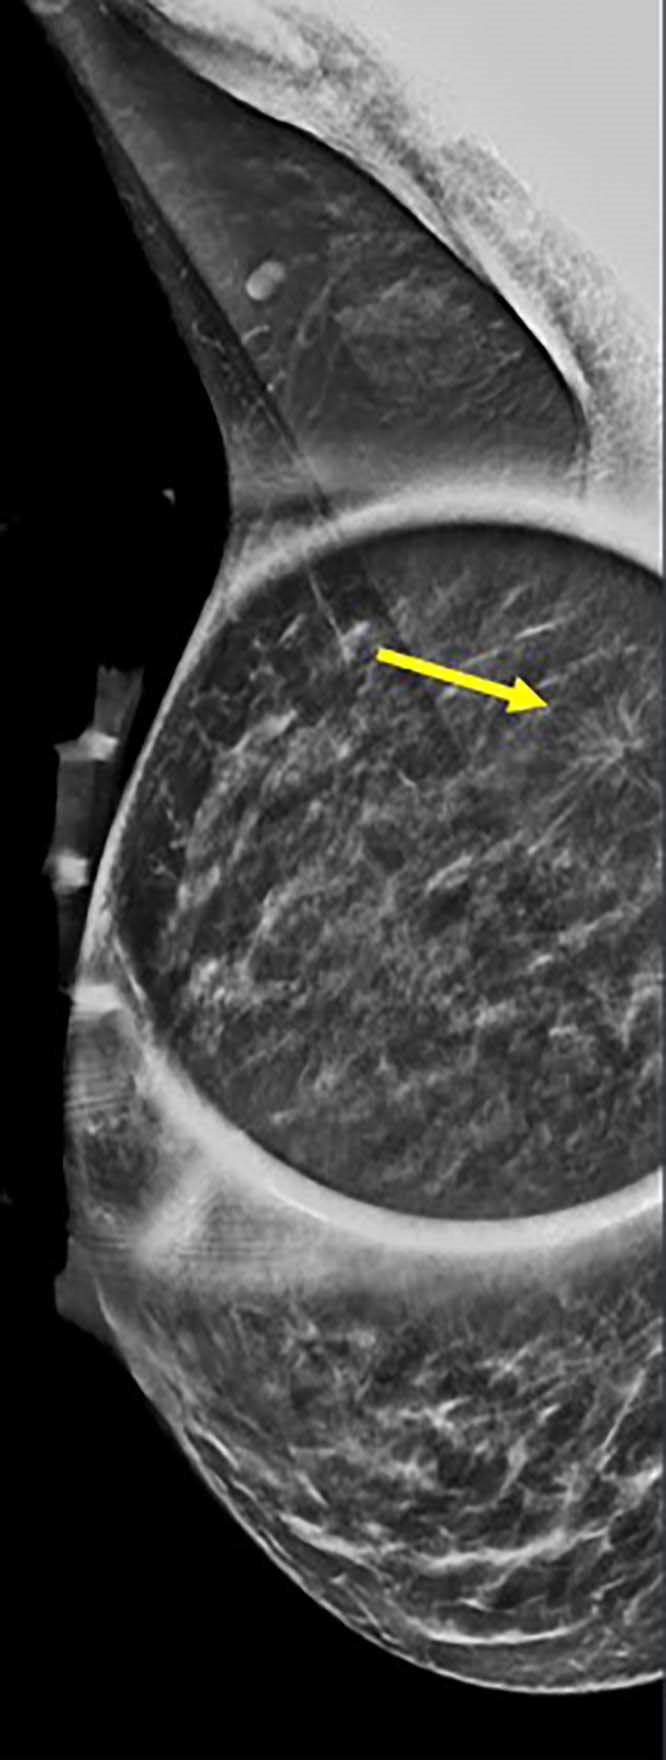

Image credit: Stamatia Destounis, M.D., and RSNA

A total of 1,799 breast cancers were diagnosed in 1,290 women, aged 18 to 49. Annual breast cancer diagnoses in this group ranged from 145 to 196, with a mean age at diagnosis of 42.6 years (range 23-49). Of these, 731 (41%) were detected on screening and 1,068 (59%) on diagnostic evaluation. There were 1,451 invasive cancer cases (80.7%), and 347 (19.3%) non-invasive cancer cases. “Most of these cancers were invasive, meaning they could spread beyond the breast, and many were aggressive types—especially in women under 40,” Dr. Destounis said. “Some were ‘triple-negative,’ a form of breast cancer that is harder to treat because it doesn’t respond to common hormone-based therapies.”

Even though women under 50 made up 21% to 25% of the patients that were screened yearly, they consistently accounted for one out of every four breast cancers found each year. “This is striking because it shows that younger women not only carry a stable and substantial share of the breast cancer burden, but their tumors are often biologically aggressive,” she said. “That combination—steady incidence plus disproportionately aggressive biology—directly challenges age-based screening cutoffs and strengthens the case for earlier, risk-tailored screening approaches.”